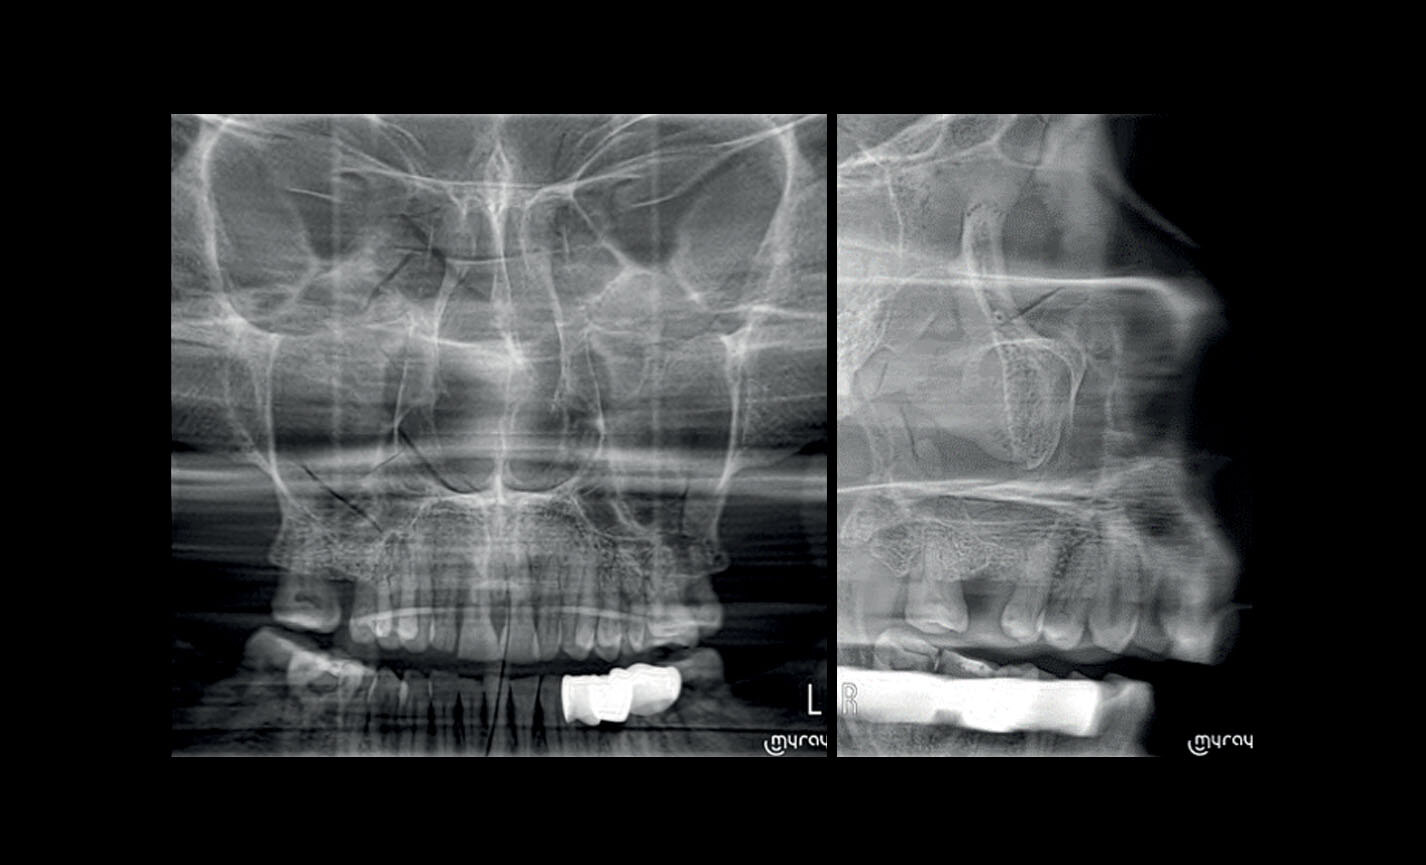

Articulations temporo-mandibulaires : droite et gauche, bouche ouverte ou fermée et en projection latéro-latérale et postéro-antérieure avec projection multi-angulaire.

Sinus maxillaires : vue de face, latérale droite et gauche, avec trajectoire optimisée.